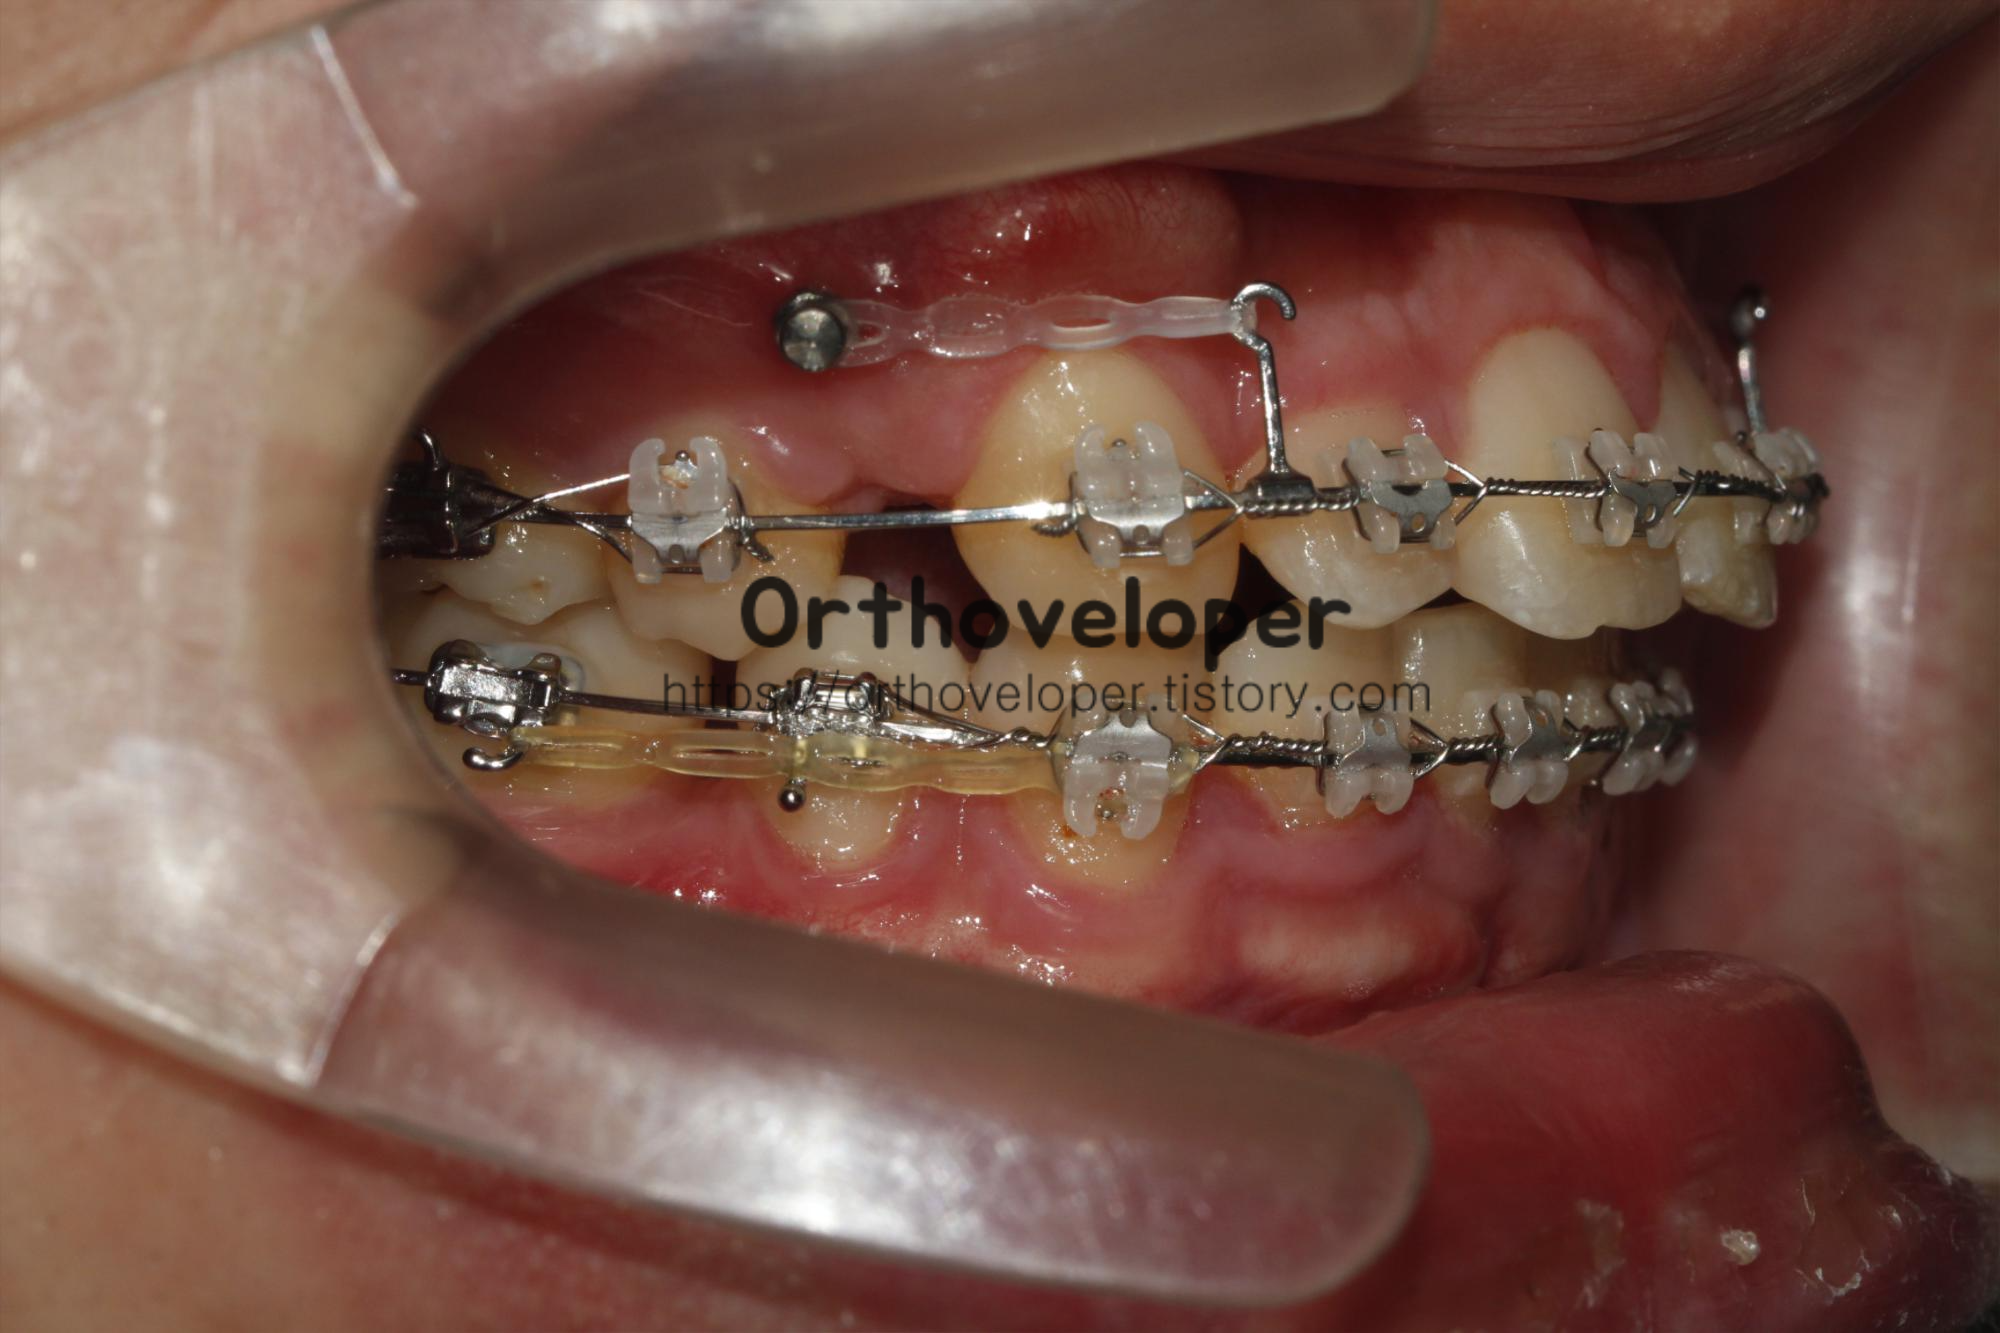

교정용 임플란트는 작은 나사못과 같이 생겼다.

교정용 임플란트를 교정치료에 사용한지는 오래되지 않았다.

교정용 임플란트를 사용은 교정치료에 혁명적인 변화를 불러왔다.

기존에는 치아와 치아끼리 서로 밀고 당길 수밖에 없어서, 불필요하게 다른 치아들이 움직이는 부작용이 있었다.

이러한 부작용을 없애고 최대의 효과를 얻기 위해 사용하는 장치라고 볼 수 있다.

간단한 국소 마취 후 직접 잇몸에 식립하게 되며, 교정치료가 끝나면 마취 없이 가볍게 제거할 수 있다.

교정용 임플란트 제거 시, 흉터도 거의 남지 않으며 치유도 굉장히 빨리 된다.